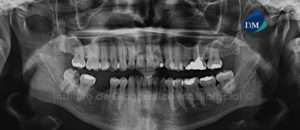

Paciente masculino, 54 años es referido al Instituto de Diagnóstico Maxilofacial para planificación de cirugía guiada con el objetivo de colocar implantes dentales en el